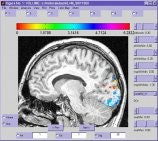

A cross section of the brain viewed using in-house data analysis tools. The colored areas represent regions that were activated by a visual stimulus presented to the subject during an fMRI scan.